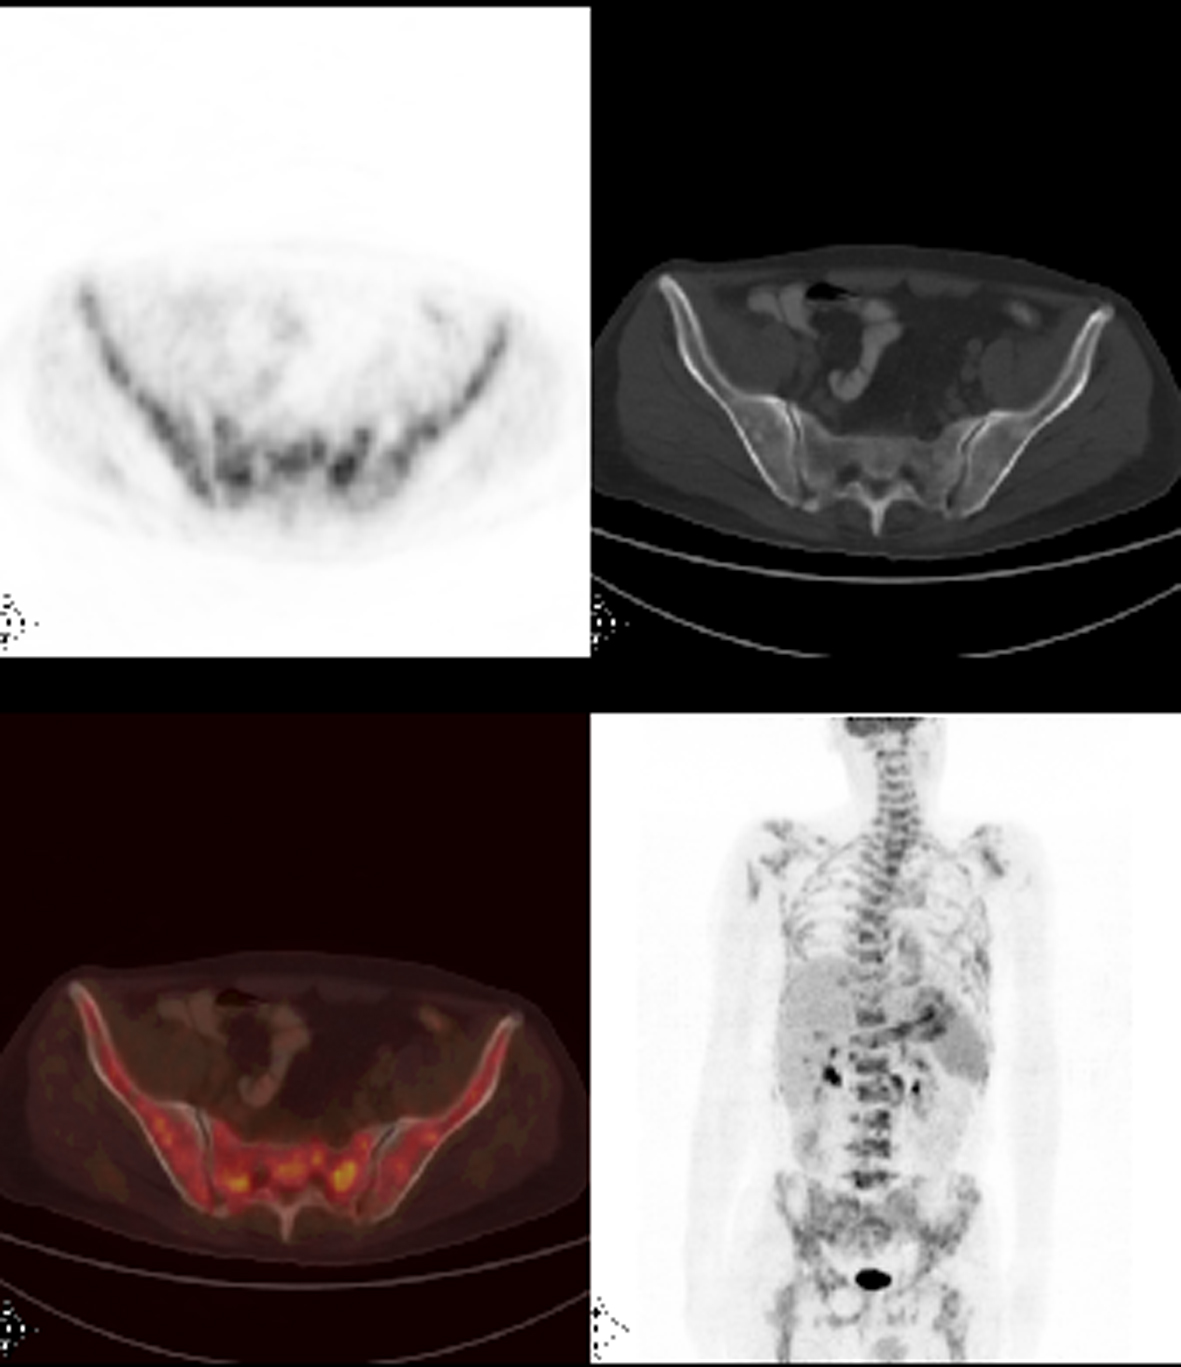

Patient 1

A 46-year-old male patient presented with fatigue, weight loss, anemia and dyspeptic complaints for the last 2 months. Gastric cancer was diagnosed with upper endoscopic biopsy. FDG-PET/CT was ordered in order to initial staging. PET/CT images not only demonstrated increased FDG accumulation at the primary tumor site but also revealed multiple metastatic intraabdominal lymphadenopathies and left supraclavicular lymph node. Heterogeneous widespread FDG uptake in the axial skeleton suggested bone marrow involvement (Fig. 1). Hgb was 9.5 g/dL; WBC, 4,100 and PLT, 33,000 per µL. Bone marrow biopsy showed metastatic gastric cancer.

![]() Click for large image | Figure 1. Axial PET/CT and MIP (maximum intensity projection) FDG PET/CT images revealed heterogeneously widespread increased FDG uptake at the skeleton which suggests bone marrow involvement. |